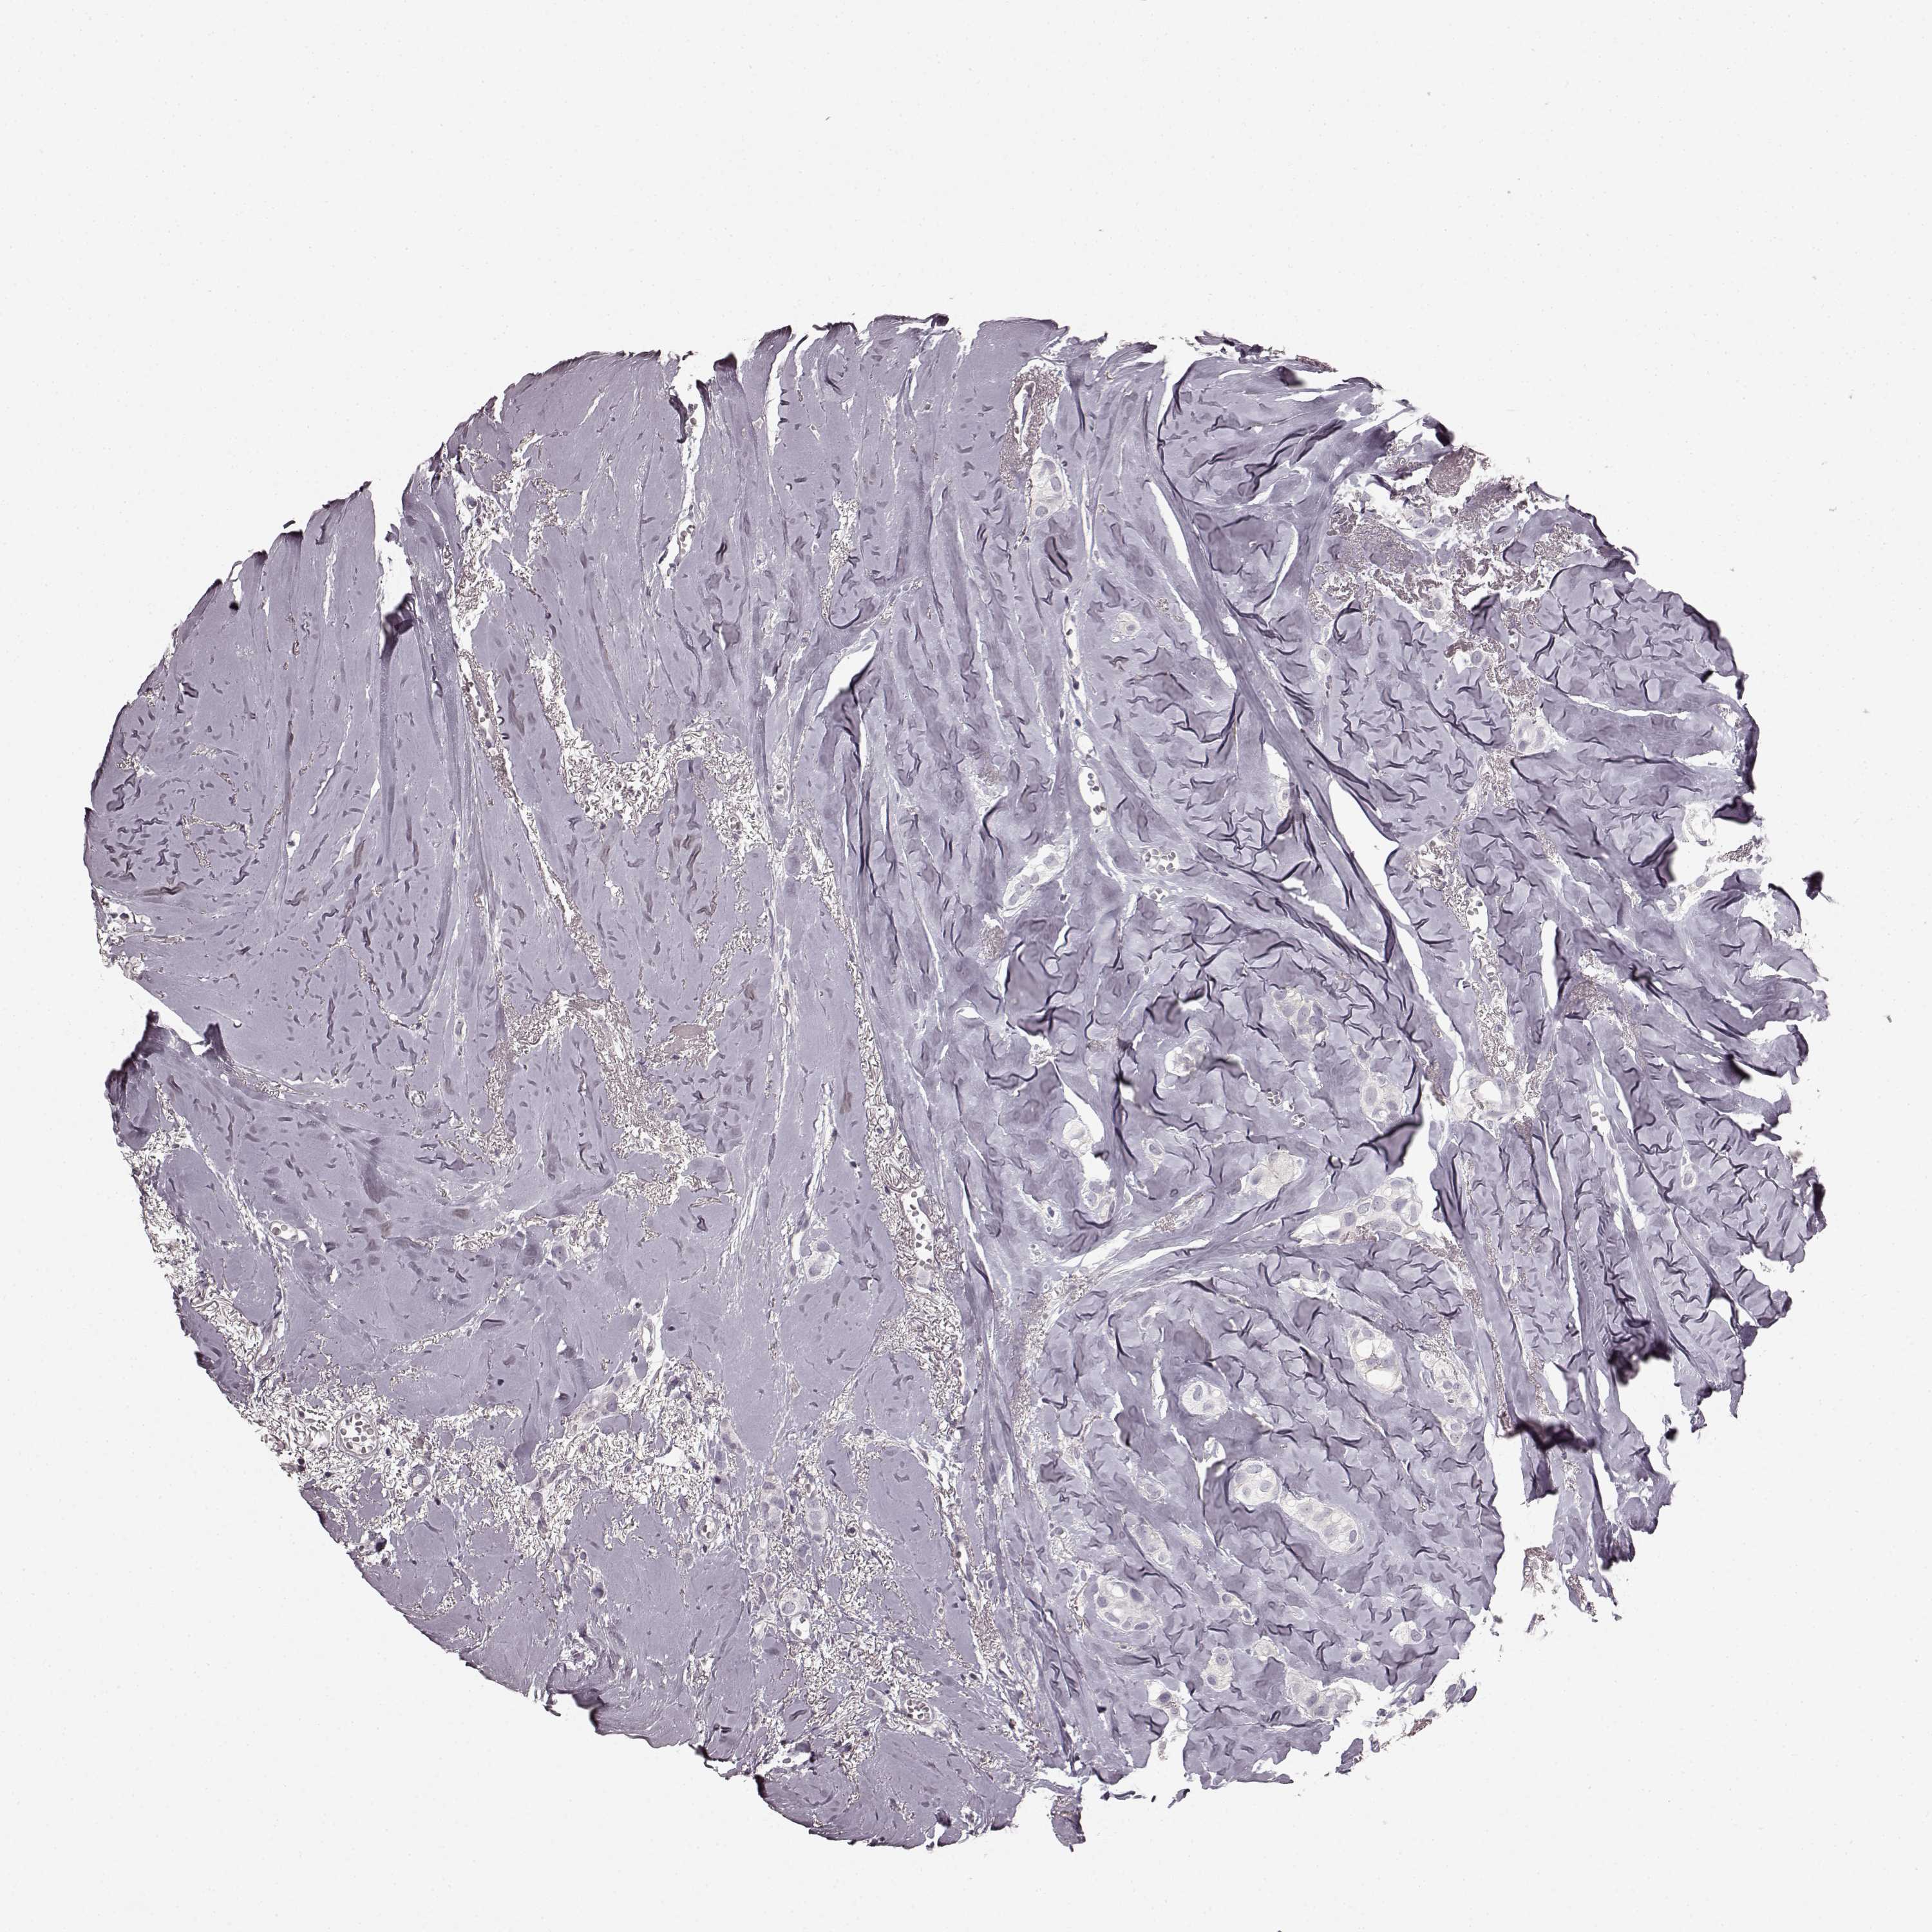

CANCER BREAST CANCER Show tissue menu

BRCA TCGA BRCA VALIDATION PROTEIN EXPRESSION

ANTIBODIES

AND

VALIDATION